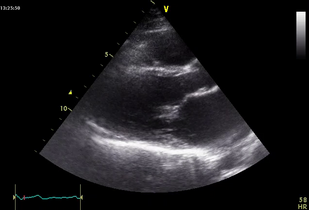

• Обложка: Ревматический тяжелый митральный стеноз (рис. 7.2)